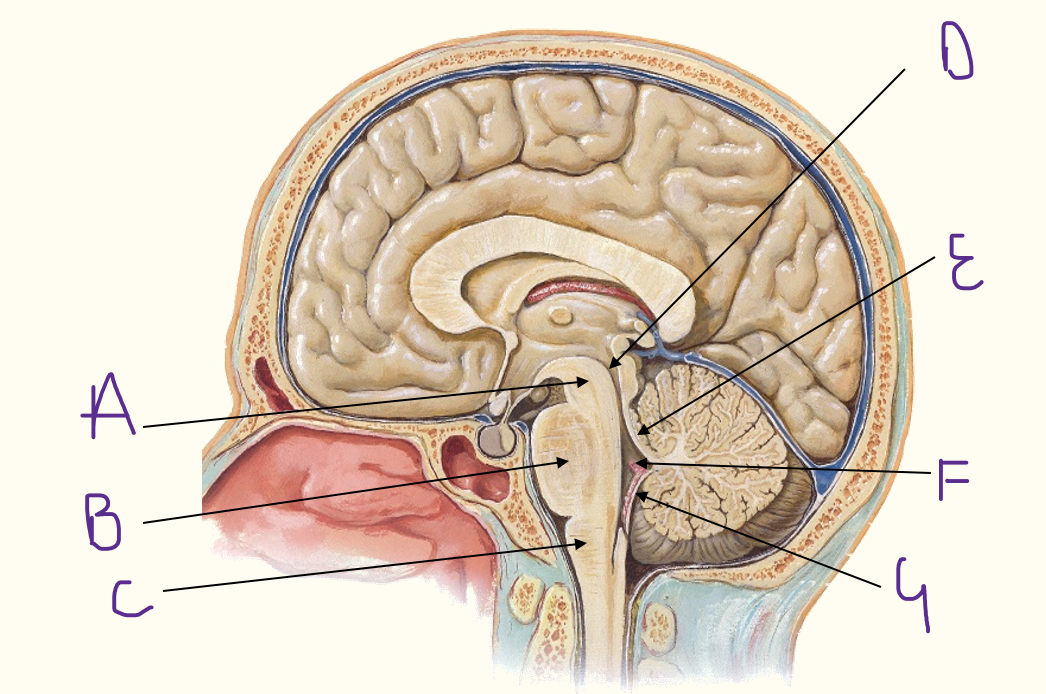

v) label picture A-G

v) A = midbrain

B = pons

C = medulla

D = cerebral aqueduct

E = sup medullary velum

F = fourth ventricle

G = inf medullary velum